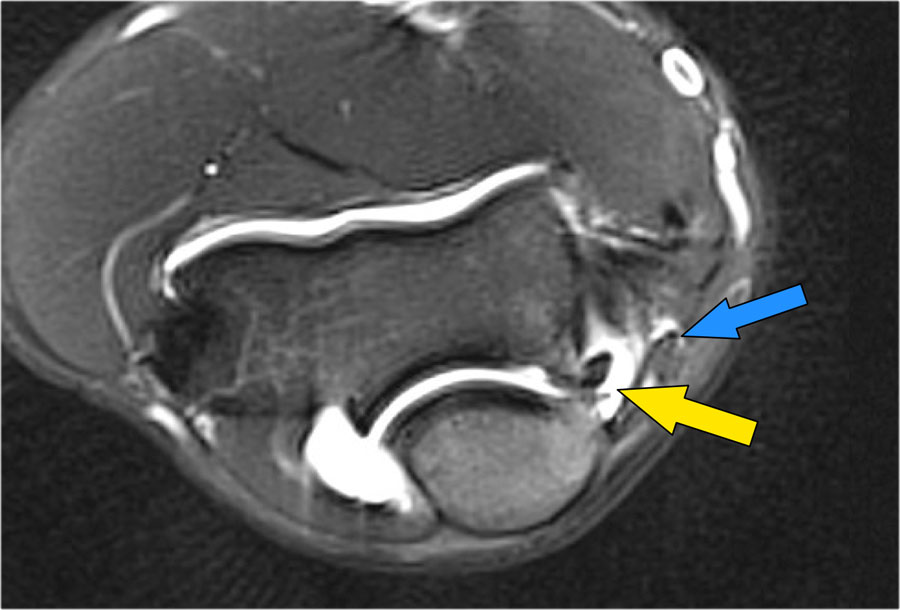

Trên hình ảnh mặt cắt ngang, chúng ta thấy rõ bó trước bình thường (mũi tên đỏ).

Chỉ có một ít phù nề bên cạnh nó.

Tuy nhiên bó sau không bình thường.

Đây là rách một phần.

Chúng tôi thỉnh thoảng gặp trường hợp này ở các vận động viên ném, khi bó trước còn nguyên vẹn và khuỷu tay của họ không mất vững.

Họ đã bị rách bó sau theo một cách nào đó, gây ra đau đớn.

Họ không cần phẫu thuật, nhưng điều này vẫn có thể khiến họ phải nghỉ thi đấu trong một thời gian khá dài.